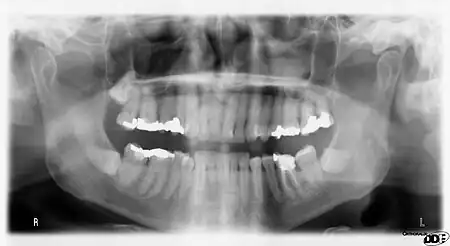

Orthopantomograms (OPTs) are used by health care professionals to provide information on:

- Impacted wisdom teeth diagnosis and treatment planning - the most common use is to determine the status of wisdom teeth and trauma to the jaws.

- Periodontal bone loss and periapical involvement.

- Finding the source of dental pain, and when carrying out tooth-by-tooth diagnosis.

- Assessment for the placement of dental implants

- Orthodontic assessment. pre and post operative

- Diagnosis of developmental anomalies such as cherubism, cleido cranial dysplasia

- Carcinoma in relation to the jaws

- Temporomandibular joint dysfunctions and ankylosis.

- Diagnosis of osteosarcoma, ameloblastoma, renal osteodystrophy affecting jaws and hypophosphatemia.

- Diagnosis, and pre- and post-surgical assessment of oral and maxillofacial trauma, e.g. dentoalveolar fractures and mandibular fractures.

- Salivary stones (Sialolithiasis).

- Other diagnostic and treatment applications.[2]